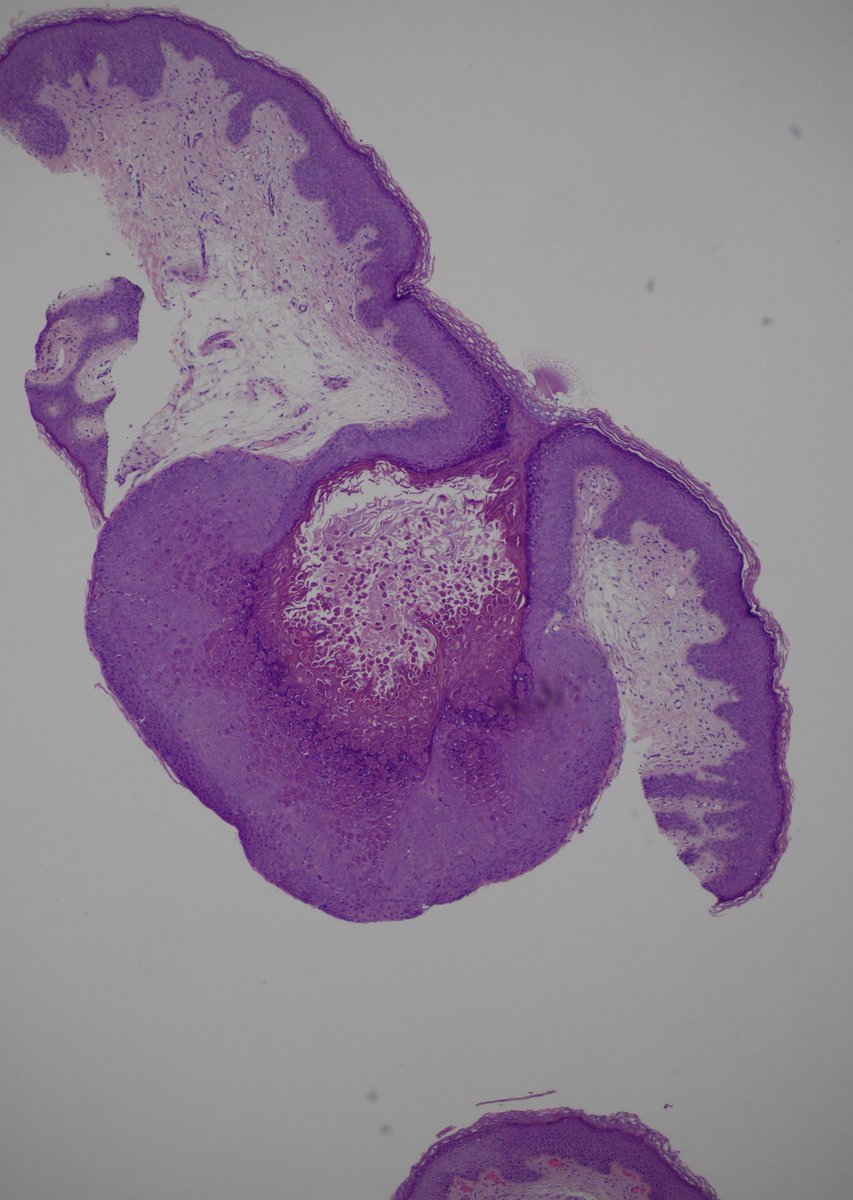

Case from last week. Multiple caecal polyps with plaque- like appearance; rule out malignancy. Nice example of Malakoplakia presenting as caecal polyps.

#gipath#idpath pic.twitter.com/sD8l5wSXMd